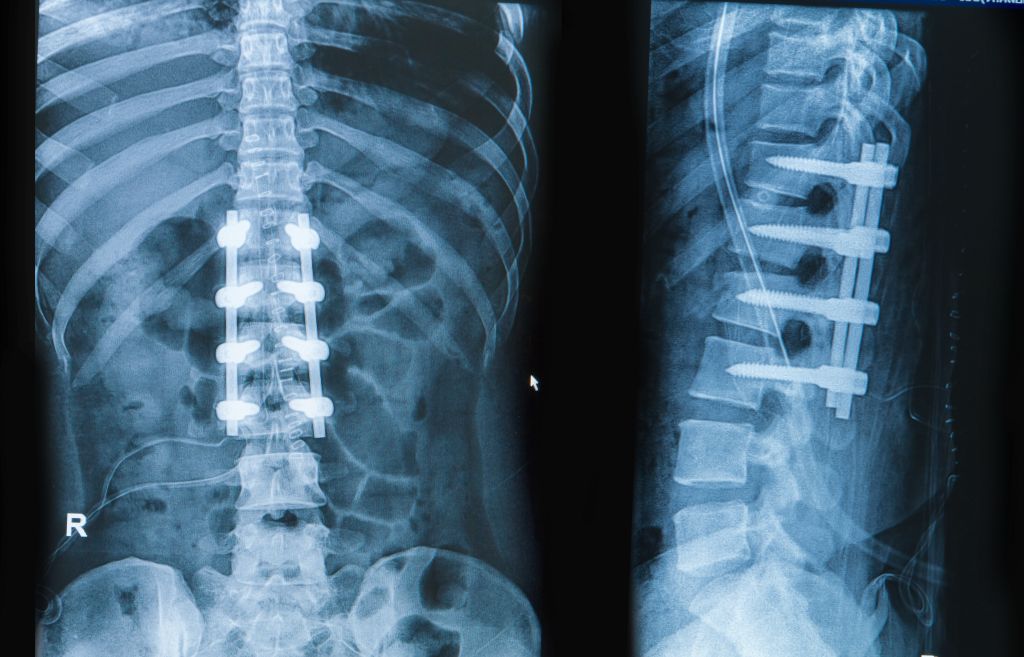

How Long After A Spinal Fusion Can You Bend . By 4 to 6 weeks after lumbar fusion surgery, most patients are cleared to return to school or work that does not involve physical labor. Most people remain in the hospital for 3 or 4 days after surgery to monitor immediate recovery. In some situations where the nerves had significant. Spinal fusion involves fusing two or more vertebrae together, eliminating the natural flexibility and range of motion in that part of the spine. A doctor may recommend gentle walking and carrying out basic daily. This loss of flexibility can. For most people, you can expect that six months after spinal fusion, you’ll be back to full activity. See rehabilitation following lumbar fusion The fusion process takes anywhere between 18 months and three years. As long as it has been cleared by the surgeon, the patient can start doing more of the following: Light chores around the home; Spinal fusion is a common form of back surgery used to treat several kinds of back problems, including scoliosis, vertebral. How long after back surgery can you bend over? A common question patients have when considering a spinal fusion surgery is how much will mobility be reduced following the. Complete recovery from spinal fusion surgery usually takes up to 8 months, with the bone continuing to evolve for 12 to 18 months.